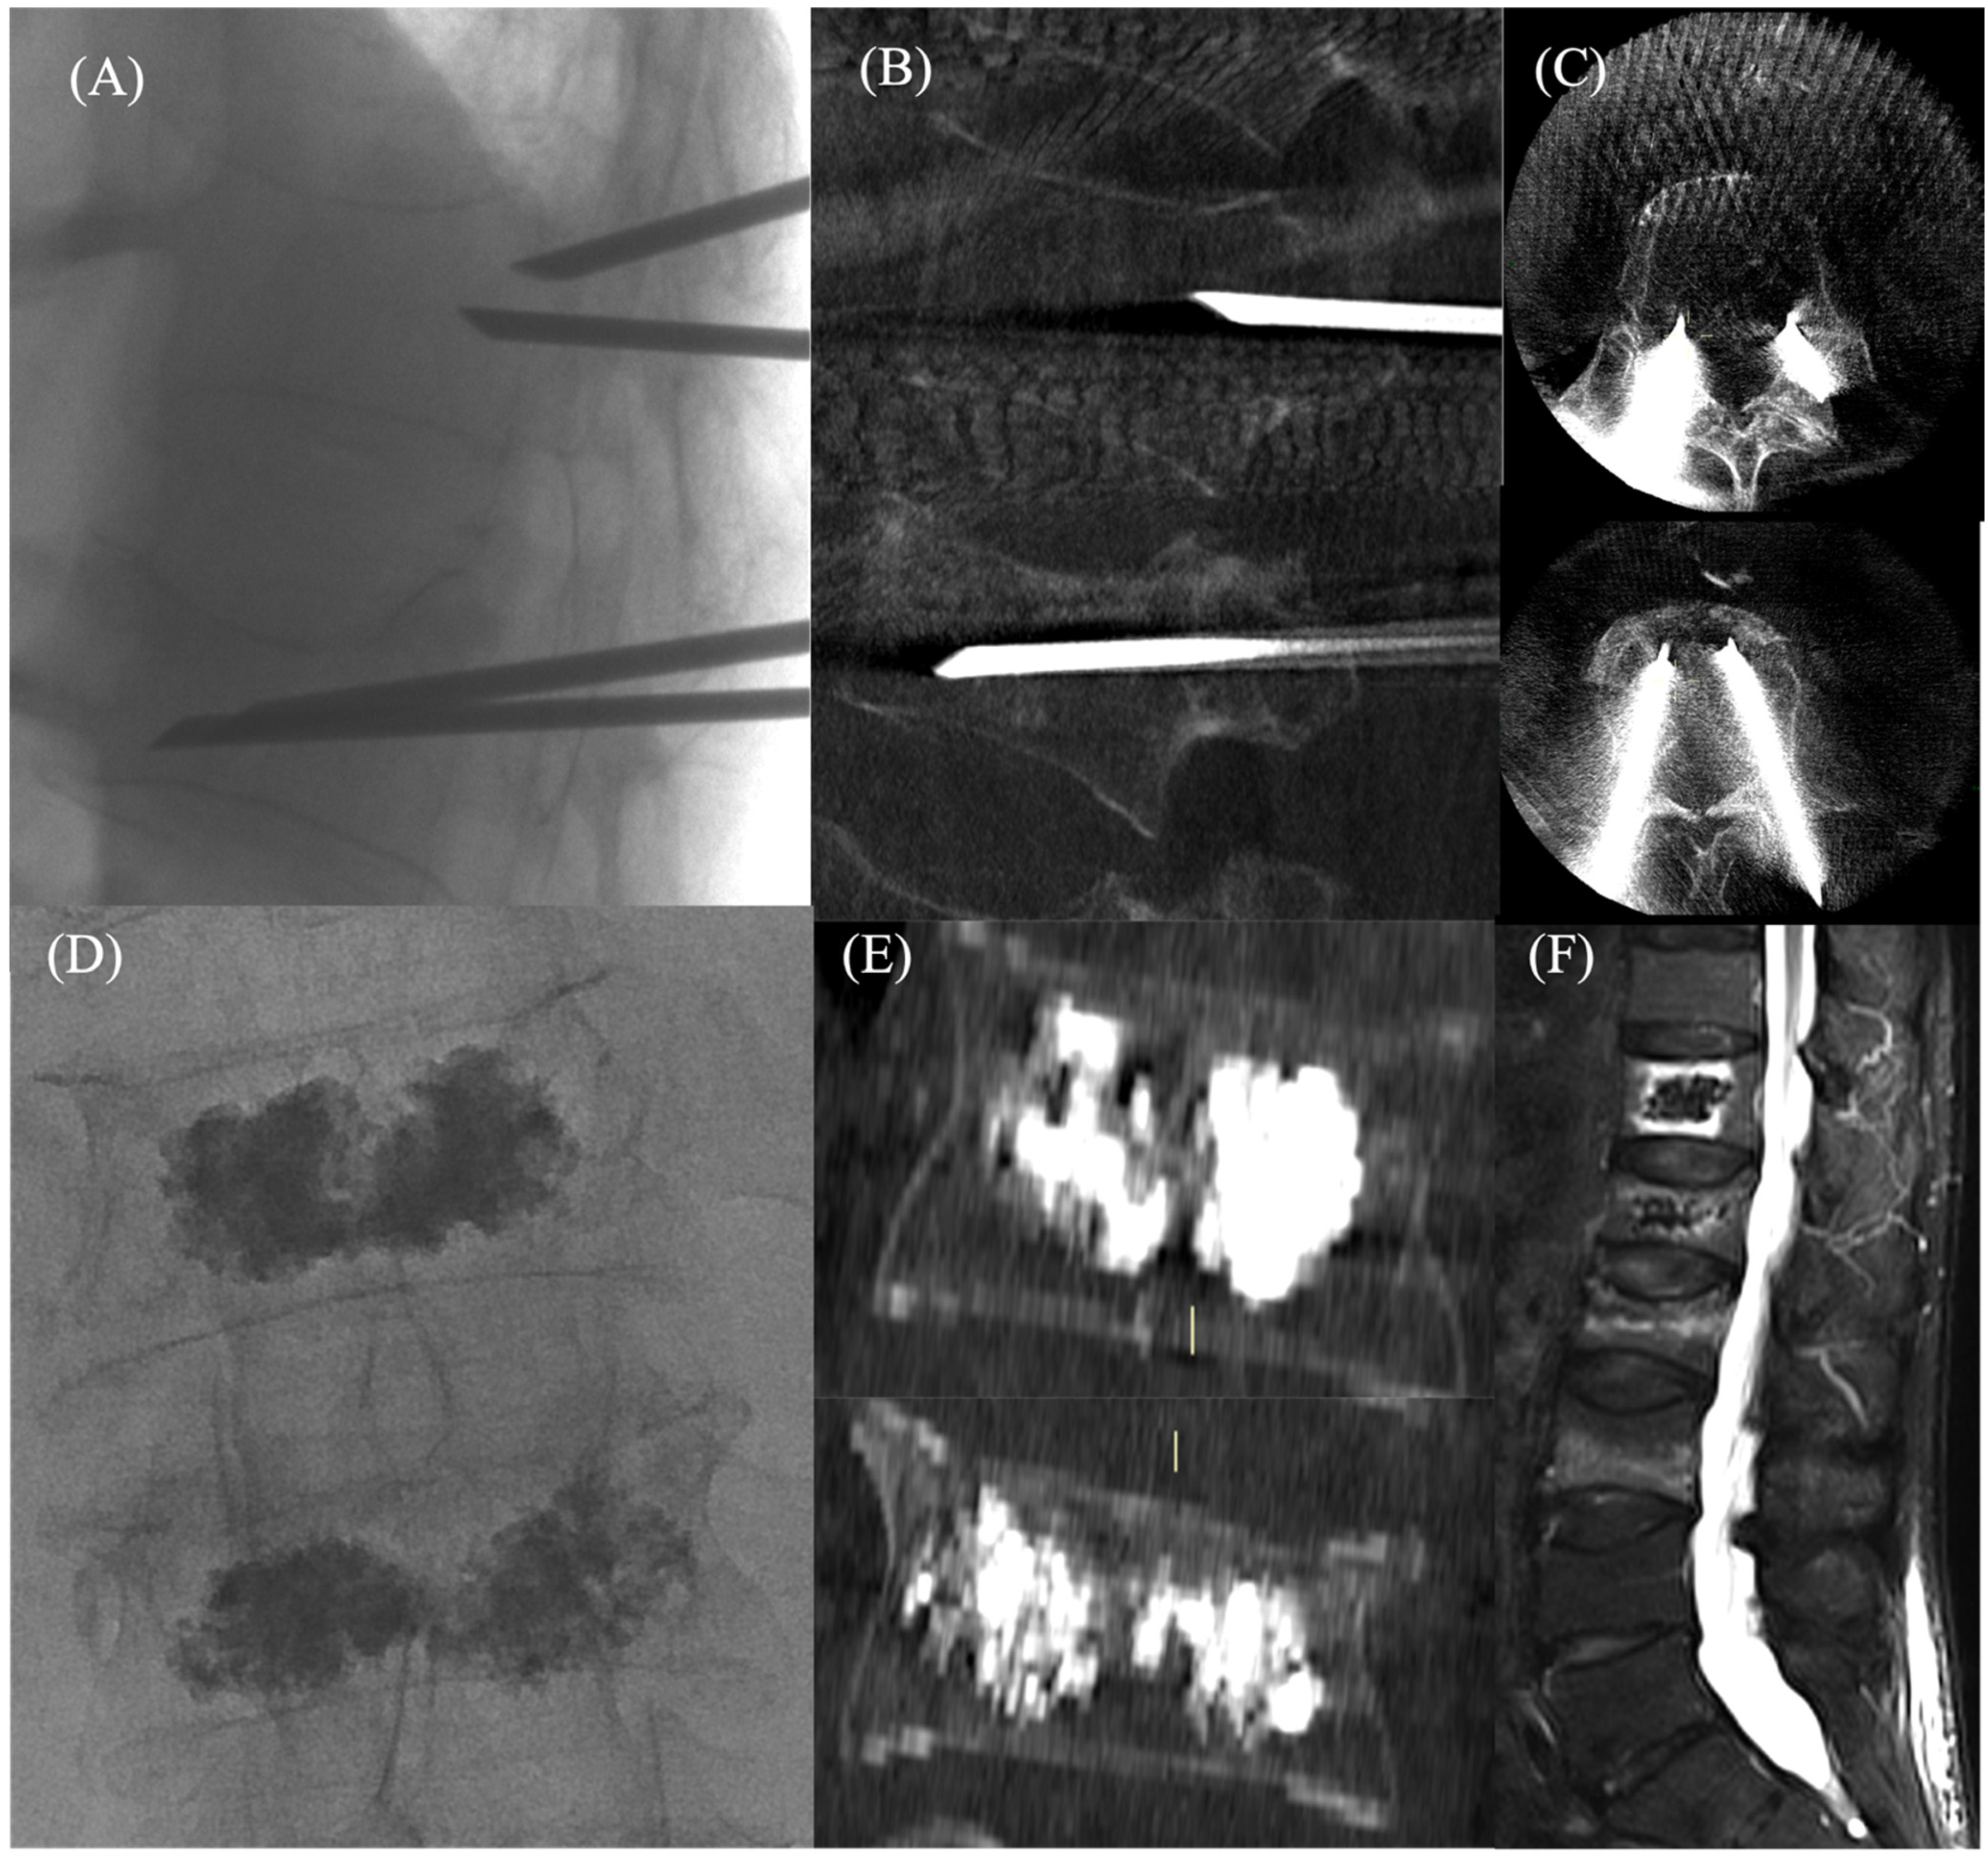

Figure 1.

F: 70 yo, with spontaneous D12 and L1 vertebral compression fracture in osteoporotic disease: (A) Percutaneous, fluoroscopy-guided, bipedicular approach showing access and curved needle entry into D12 and L1 vertebral compression fractures; (B) sagittal and (C) axial cone-beam CT image revealing the correct positioning of the needles; (D) post-procedural anteroposterior fluoroscopic view and (E) coronal cone-beam CT images after vertebroplasty showing uniform cement distribution; (F) sagittal MRI STIR images after one month demonstrating a reduction of marrow edema into the vertebral body.